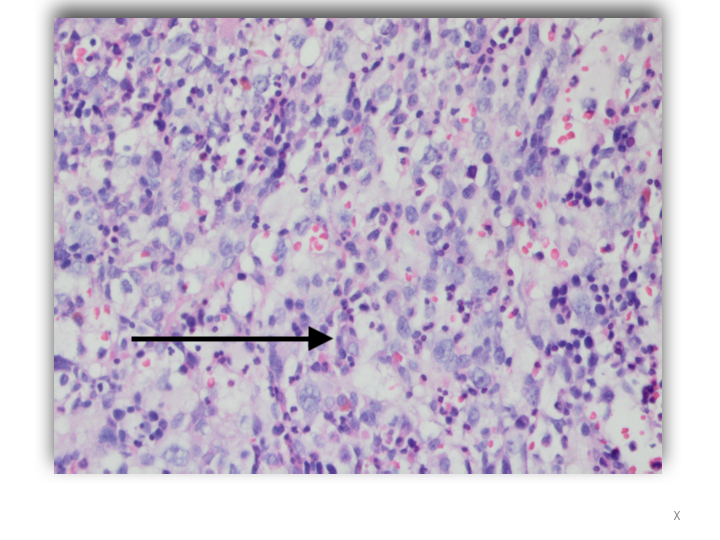

Case Presentation: A 40-year-old man presented to the Emergency Department with fatigue, progressive shortness of breath, fever and night sweats for three months. During this period, he had episodes of blurred vision and photosensitivity. A diagnosis of Vogt Koyanagi Harada uveitis was made following an ophthalmologic assessment. He was treated with prednisone 40mg daily. Physical examination revealed oral candidiasis and splenomegaly. He had no lymphadenopathy. Laboratory studies showed Hb 7.4g/dL WBC: 5.8x 103 μL, platelets 72 x103/μL, LDH 1042 u/L, ferritin 1829 ng/L, Triglyceride 619 mg/dL and lactic acid 4.3 mmol/L. Viral serology for EBV, CMV, HIV and viral hepatitis were negative. However, he was positive for Coxsackie A IgG. Thoraco-abdominal CT confirmed splenomegaly. Vancomycin and cefepime were empirically started. The patient’s hospital course was marked by continued fevers as well as severe thrombocytopenia and anemia with a nadir of 15×103/µL and 6.8 g/dl respectively, both requiring transfusions. Blood cultures returned without growth at the end of incubation. Bone marrow biopsy was done, revealing hemophagocytosis and Diffuse Large B Cell Non-Hodgkin Lymphoma. Soluble CD25 receptor level was 2156 pg/ml. Lumbar puncture showed no central nervous system involvement. Systemic chemotherapy with dexamethasone and etoposide was commenced. Thereafter his fevers and cytopenia improved. He is currently receiving intrathecal Methotrexate for CNS prophylaxis as an outpatient.

Discussion: Hemophagocytic Lymphohistiocytosis (HLH) is a rare disease characterized by hyperproliferative macrophages which phagocytose hematopoietic elements. Its incidence is estimated to be 1: 280,000. There are two types: primary HLH is an autosomal recessive disorder affecting children most commonly within the first year of life. Secondary HLH is acquired in adults because of strong immunologic activation from systemic infection, autoimmune disease or underlying malignancy. The diagnostic criteria of fever, splenomegaly, cytopenia, hyperferritinemia, hypertriglyceridemia, soluble CD25 receptor level greater than 2400 pg/ml and hemophagocytes on bone marrow biopsy was developed for use in children and is likely less reliable in adults. The patient presented with 6/8 diagnostic criteria and a diagnosis of HLH was established. Although HLH has been reported as a sequela of Coxsackie Virus infection, the patient’s likely trigger was his lymphoma. Treatment involves controlling inflammation with corticosteroids and cyclosporin A. The use of etoposide and anti-thymocyte globulin removes activated immune cells. Treatment of underlying infections if present, supportive care with transfusions and prophylactic antimicrobials is also necessary.